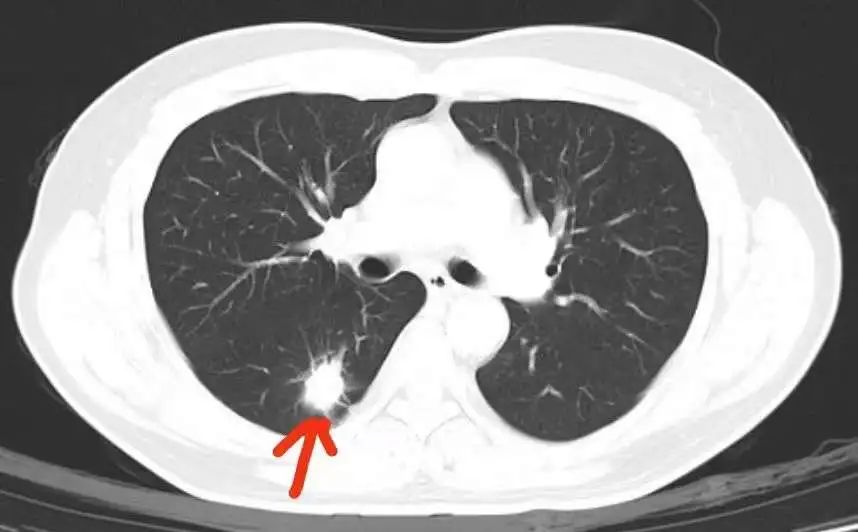

梁先生接受了医生的建议,即时前往健康管理中心医学影像区进行肺部 CT 扫描检查。当天结果回报:右肺下叶背段结节 2.5 cm 伴毛刺及胸膜牵拉,高度怀疑周围性肺癌。经医生对比后发现,肿瘤部位特殊,因 X 光分辨率及检查方法的局限性,正位及侧位分别被右侧肺门及脊柱遮挡,导致胸片难以发现肿瘤。健康管理中心再次立即启动体检重要异常结果回访程序及转诊通道,梁先生很快转入专科进行治疗。